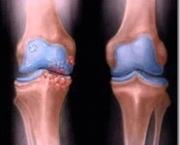

Também conhecida como gonartrose, a osteoartrose do joelho é uma enfermidade degenerativa e inflamatória que resulta na destruição da cartilagem das articulações levando à deformidades nelas. Normalmente a degeneração cartilaginosa começa com o envelhecimento do indivíduo.

De acordo com especialistas a osteoartrose do joelho é uma enfermidade crônica, que afeta as articulações axiais e periféricas que estão relacionadas com mais frequência a sustentação do peso corporal. Possui uma evolução lenta e assintomática. Alguns estudos demonstraram que o problema atinge cerca de cinco por cento das pessoas com menos de trinta anos e cerca de oitenta por cento dos indivíduos com mais de sessenta anos. Uma pesquisa realizada pela OMS (Organização Mundial de Saúde) demonstrou que a osteoartrose de joelho seria uma das principais causas de incapacidades tanto em homens quanto em mulheres. Os estudos radiográficos que foram realizados demonstraram alterações em cerca de trinta por cento em ambos os sexos, com apenas um terço desse total apresentando sintomas.